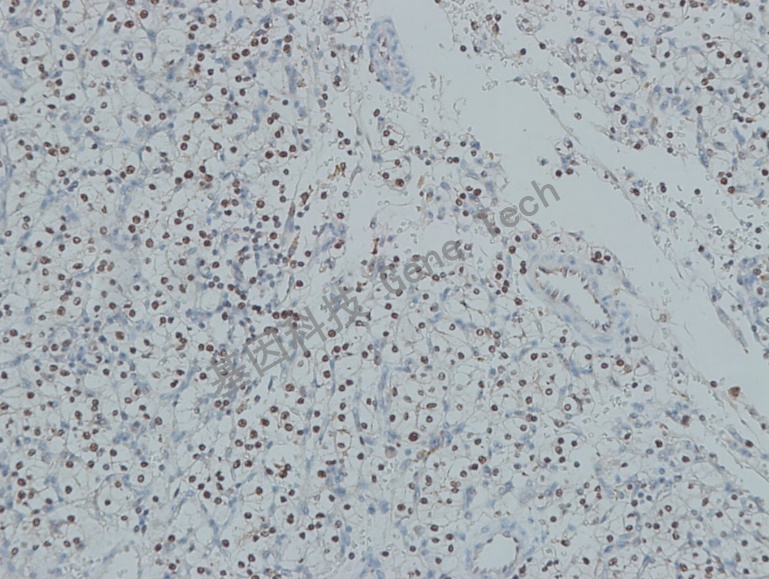

卵巢透明细胞癌石蜡切片,用 HNF1β(GT2326)染色,细胞核阳性,DAB 显色。

【阳性部位】细胞核